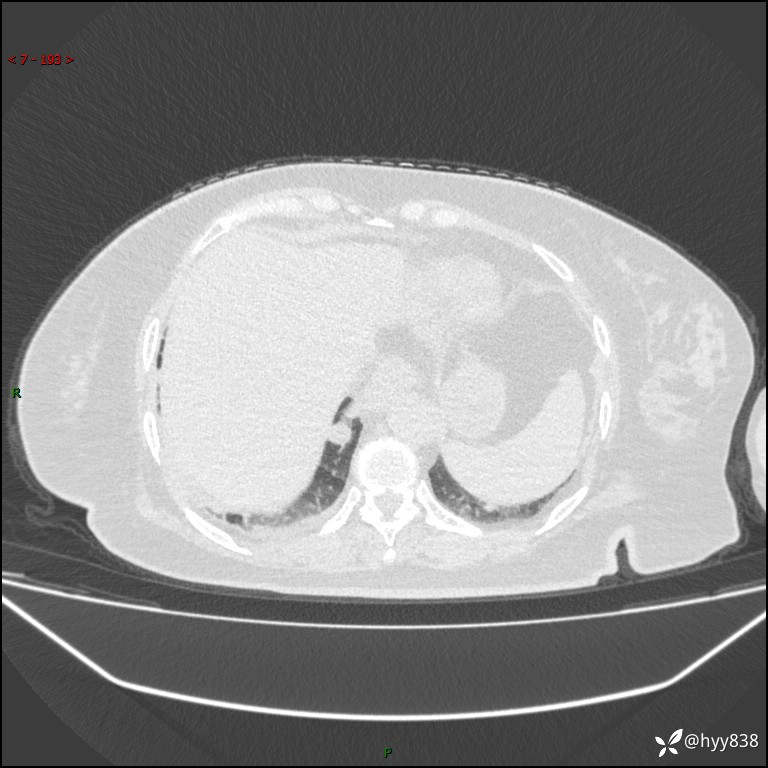

患者性别:女

患者年龄:57岁

简要病史:昏迷入院

胸部 CT平扫、